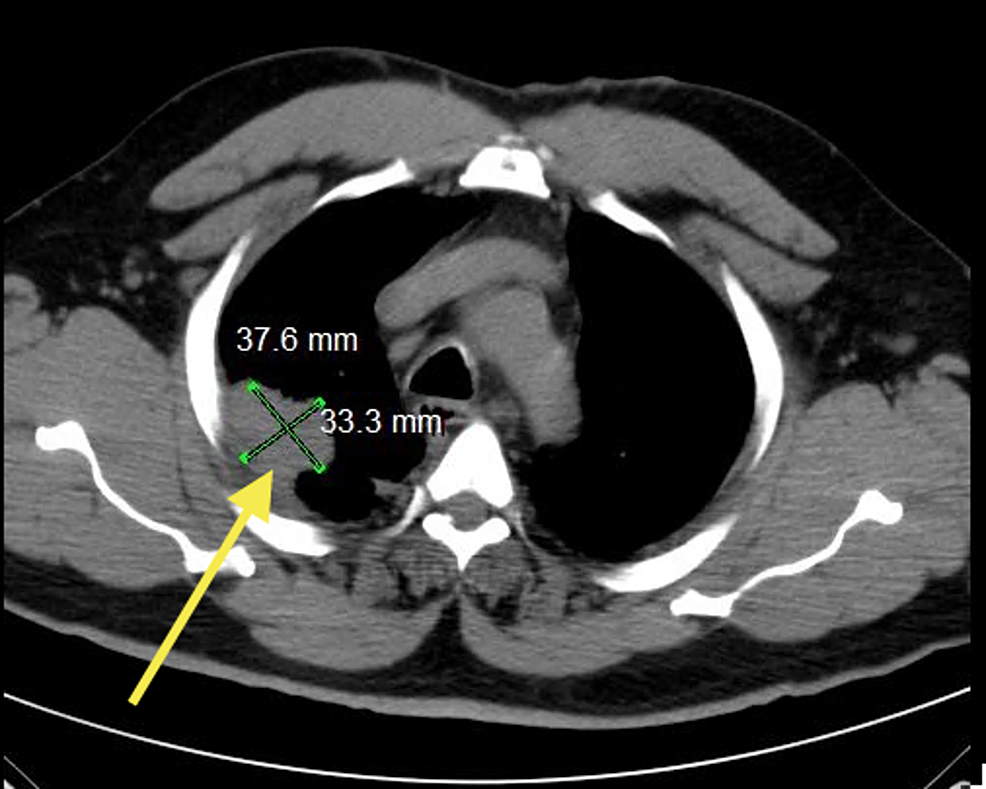

A 50-year-old male who is an established patient of ours underwent preoperative evaluation in August 2013, which revealed an abnormality not present in the imaging taken in 2011. His chest X-ray revealed a prominence in right hilum and a density along the right pleura towards the right upper lobe. Later, the patient underwent noncontrast computed tomography (CT) of the chest depicting pleural-based mass measuring 3.3 cm x 3.7 cm in the right upper lobe (Figure 1). Biopsy performed a few weeks after imaging showed adenocarcinoma,